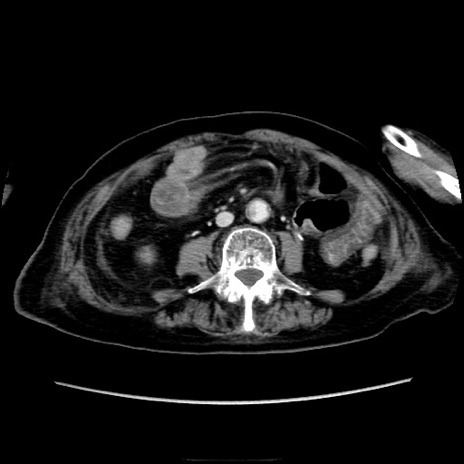

症例40(横断像)

【症例】90歳代女性

【主訴】腹痛・嘔吐

【現病歴】 食欲低下、嘔吐があり昨日他院受診。肺炎と診断され入院となる。入院後より腹部全体に圧痛あり。胃管留置され経過みていたが、症状持続するため、

当院転院となる。

【既往歴】胸椎圧迫骨折、胆石症

【身体所見】腹部:中央に激痛あり、圧痛あり、反跳痛不明

【データ】WBC 17100、CRP 18.82

横断像